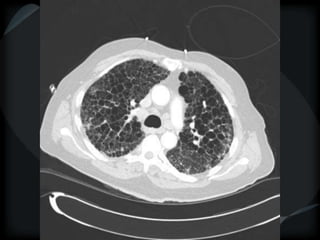

Reticular Pattern - NSIP

inflammation and fibrosis

 Predominantly basilar

 Significant ground glass

 Subpleural sparing low sensitivity, high specificity

 No honeycombing, some cystic change

 Traction Bronchiectasis

Diagnostic accuracy 50%

 Cellular NSIP

 Fibrotic NSIP

 Associated with CVD

 Undifferentiated CVD – T. King